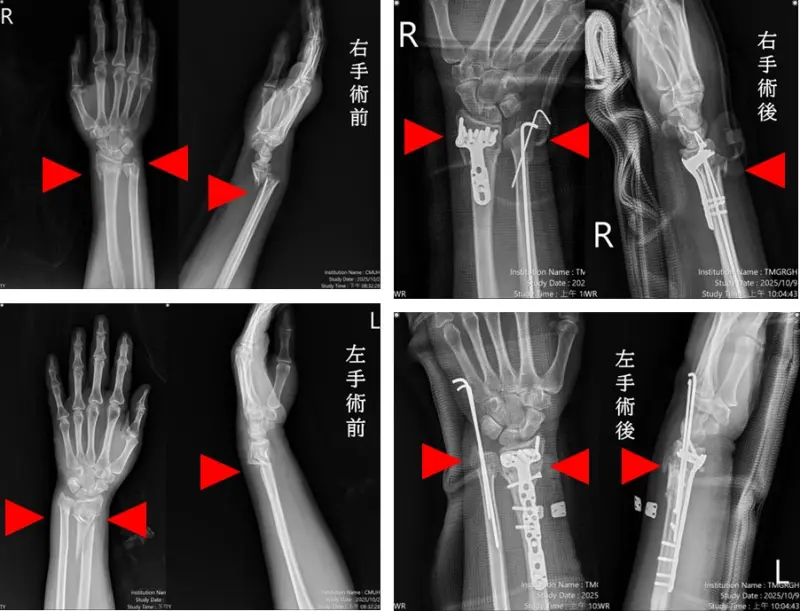

台中57歲婦人因交通事故雙手多處骨折與脫位,台中市立老人復健綜合醫院確診為粉碎且複雜性骨折,啟動「多主治醫師協同手術機制」,由骨科部蘇伯翰、江晟弘、毛睿廷三位主治醫師同步進行左右手微創手術,僅僅一個小時即完成四處骨折修復,三日後順利出院,創新醫療紀錄。

蘇伯翰醫師指出,傷患送至本院就即時進行復位與石膏固定,並於24小時內安排開刀,採用「多主治協同手術模式」,由三位主治醫師同時操作左右手四處骨折微創手術,將傳統五小時的手術時間,縮短為一小時,協同分工可加快病患恢復速度,並提升安全性。患者傷口小、出血少,三天後順利出院,恢復良好。

▲台中57歲婦人因交通事故雙手多處骨折與脫位,市醫3名主治協同手術,一小時修復大幅減輕傷患出血風險。(圖/市醫提供) 蘇伯翰說,創新協同手術模式為本院特色之一,整合各專科醫師團隊,將過往需單人分段完成的多部位骨折手術,轉化為多主治醫師並行執刀,讓手術時間與麻醉時間同步縮短,進而降低併發症與出血風險。此模式也減輕護理與麻醉科人員負擔,讓手術室與病房運作更有效率,成為醫療人力吃緊時代的重要解方。